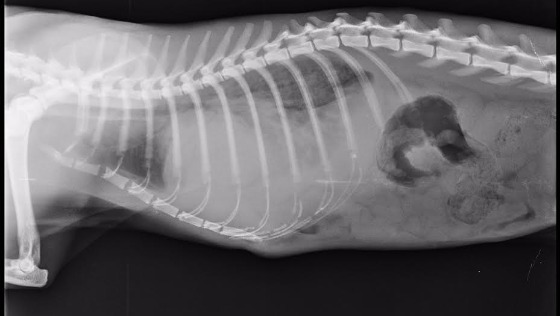

Zdjęcie rentgenowskie było niepokojące: przepuklina przeponowa z przesunięciem organów, duży ucisk na płuca. Rokowania ostrożne. Podczas operacji, na którą się zdecydowaliśmy (bo Kocik żył już właściwie na ćwierć oddechu, a i takie życie nie było zbyt pewne), okazało się, że jest gorzej. Przerwane zostały oba płaty przepony, przesunął się żołądek i trzustka, a również przesunięta wątroba przyrosła do przepony i mostka.